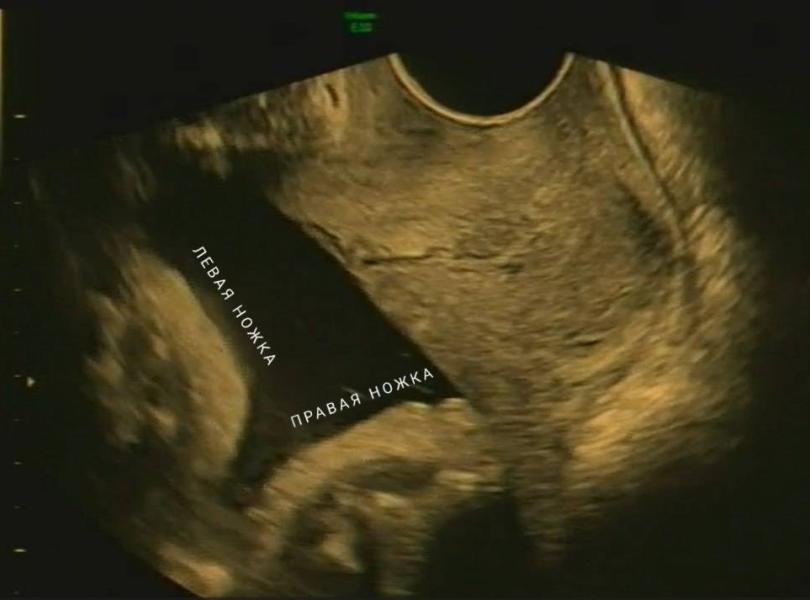

«Да какая же у вас тут головка,я вижу тут пяточки!» - заявляет врач УЗИ вводя мне трансвагинальный датчик. Мысли роем устремляются в мою голову, как же ножки, ведь неделю назад мне Романовский сказал, что головное предлежание и перевернуться он уже не может. Особенности понимаете ли – крупный плод, да и я сама худая, места нет для переворота.

Молча наблюдаю за врачом, как она меняет датчики и густым слоем покрывает мой живот холодным гелем. «Ох, а вот и головка, да как же он умудрился так ноги на голову то задрать!!!».. Фух, мысленно выдыхаю я, малыш все же в головном и беспокоиться пока не о чем! Напугал, малый.

Замеряет параметры, второй врач под диктовку вводит данные. «Что-то тут не то» - говорит- «Слишком большой для срока», замеряет заново окружность животика, головки, доходит до ножек – «Да он какой у вас длинноногий» - заводит параметры, где выдает программа, что ножки и ручки на 41 неделю. Не удивительно, думаю я,что он так ноги то задрал.

УЗИ было в 34 недели. А сегодня 35. Очередной чекпоинт пройден, следующий в 37 недель (доношенная беременность).